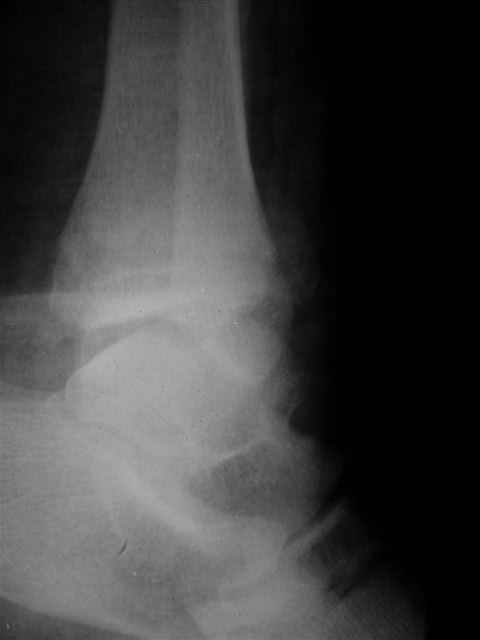

Я предупреждал, что ничего сверхъестественного. Каюсь, что одна из спиц прошла несколько дальше, чем нужно было, но главное - перелом стабилизирован и больной работает суставом в полном объёме, несмотря на представленную раннее травму коленного сустава.